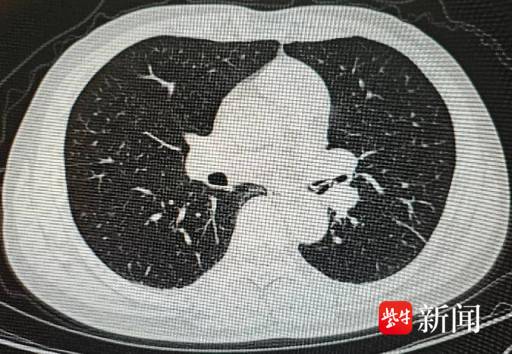

当天聚餐后,李先生突然出现严重咳嗽症状,当地医院检查后发现,其气道内有高密度异物,情况不容乐观,随即紧急转往江苏省人民医院(南京医科大学第一附属医院、江苏省妇幼保健院)急诊求助。急诊紧急联系呼吸与危重症医学科值班医生进行会诊。

手术过程中,医护人员发现,李先生左主支气管远端有一枚巨大且尖锐的骨样异物,已经嵌顿进支气管管壁,周围还有密集的血管,稍有不慎就可能引发危险。朱毅副主任医师凭借丰富的临床经验和仔细小心操作,成功将这枚异物取出。

令人意外的是,手术中还发现,李先生左上叶、左下叶开口等处,还同时另有三枚尖锐的骨样异物嵌顿,朱毅副主任医师逐一小心将其取出。术后经确认,这些嵌顿的异物均为锐利的鱼刺。